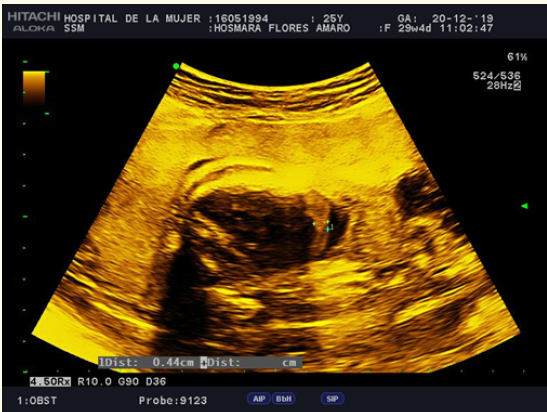

Persistence of the Left Superior Vena Cava with Absence of the Right Superior Vena Cava: Fetal diagnosis and postnatal evolution

Antonio Sánchez Andrés, Reguillo LaCruz A, Gil Beltrán E and Carrasco Moreno JI. 11(11): 10-15.